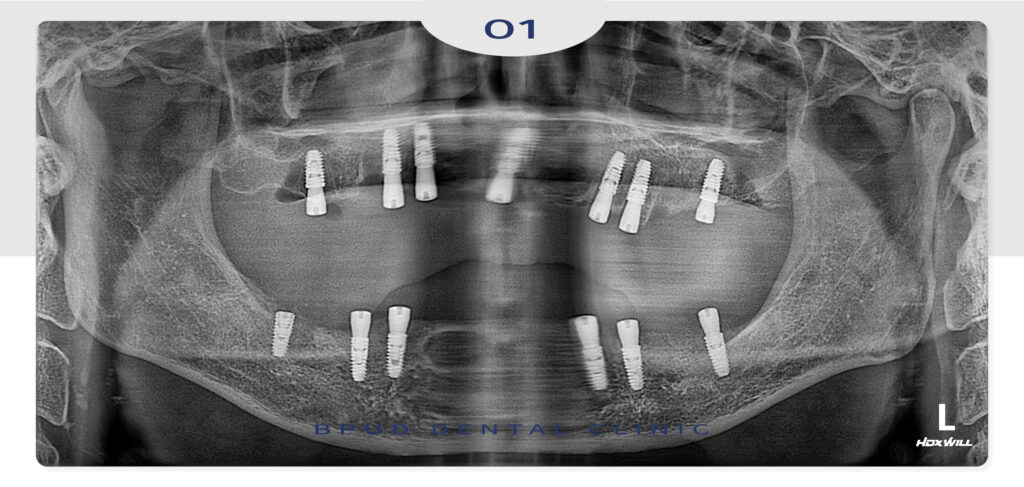

상악은 7개, 하악은 6개 임플란트 식립 후

전체 수복 계획입니다.

양쪽 위쪽은 뼈가 부족하여 상악동 거상술을

동반하여 식립을 진행하였고

아래쪽 앞니에는 물혹이 있어

낭종적출술 시행 후 골이식까지 진행하였습니다.